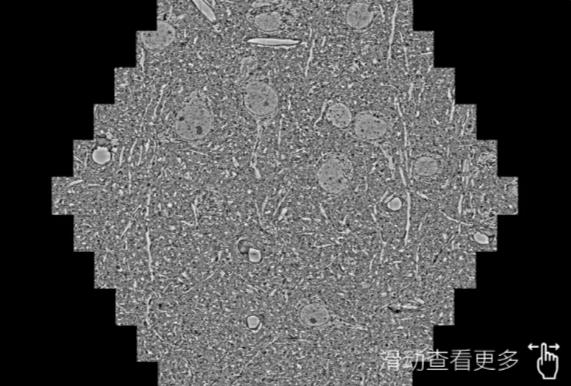

鼠脑切片。左图使用东丽蔡司东丽扫描电镜MultiSEM706对165μmx143pm面积区域成像,耗时仅需1.5秒。右图为鼠脑切片中30μm区域放大效果。样品由芝加哥大学B.Kasthuri提供。

使用蔡司高速东丽扫描电镜MultiSEM对1mm²人脑皮层组织进行高分辨成像,并对其中的各种细胞结构进行三维重构分析。左图展示了2x3mm²组织平面中锥体神经元的三维重构效果。右图显示了局部体积神经元三维重构。图像由哈佛大学chtman实验室提供,渲染图由D. Berger 制作。